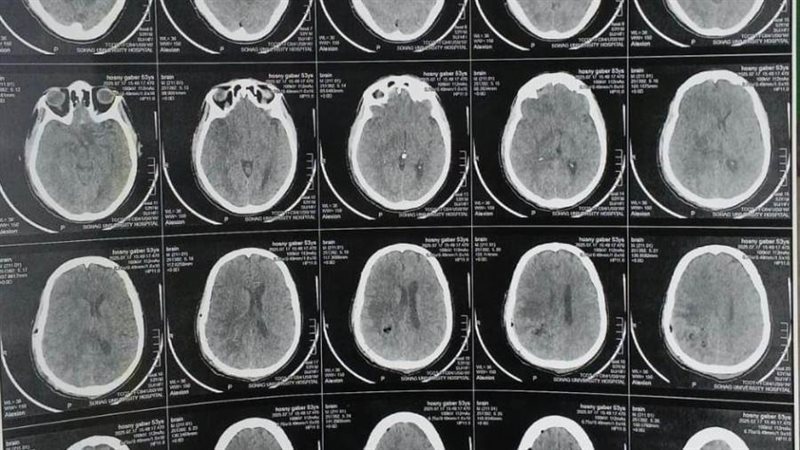

ومن جانبه، أوضح الدكتور مجدي القاضي، عميد كلية الطب البشري ورئيس مجلس إدارة المستشفيات الجامعية، أن المريض كان يعاني من اضطراب بدرجة الوعي وشلل نصفي بالجانب الأيسر، وتبين من الفحوصات وجود ورم بالمخ بحجم ٧×٥×٤ سم، وقد تم استئصاله بالكامل خلال جراحة استغرقت ٤ ساعات، مشيرًا إلى أن الفريق الجراحي استخدم تقنية حديثة تعتمد على حقن الصبغات الورمية لتحديد حدود الورم بدقة.

وأشار الدكتور أحمد كمال عبدالحميد، المدير التنفيذي للمستشفيات الجامعية واستاذ جراحة المخ والأعصاب والعمود الفقري، والذي أجرى الجراحة، إلى أن العملية تمت باستخدام ميكروسكوب جراحي متطور، والحفار الكهربائي لفتح عظام الجمجمة، مما ساهم في الوصول الآمن إلى الورم واستئصاله بالكامل دون التأثير على الأنسجة الحيوية. مضيفًا أن المريض استعاد وعيه بالكامل بعد الجراحة، وعادت حركة الأطراف إلى طبيعتها.